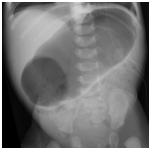

40. 新生兒出生2 星期開始食後噴射性嘔吐,1個月大求診, 這張影像的最佳診斷是? (A)Jejunal Atresia。 (B)Duodenal Atresia。 (C)Meconium Plug Syndrome。 (D)Hirschsprung Disease。 (E)Infantile Hypertrophic Pyloric Stenosis。